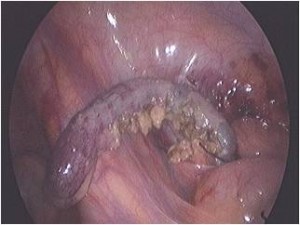

The commonly misleading history given by the parents is that the child may have had a trivial trauma or an insect bite. However, for the clinician the golden rule should be ‘Any acute scrotum is testicular torsion unless proved otherwise’. Investigations like ultrasound and color doppler may be done to help in the diagnosis. However, in the event of any doubt, it is safest to do a surgical exploration of the scrotum. The other uncommon causes of acute scrotum are acute epidydymo orchitis, scrotal abscess, idiopathic scrotal oedema and torsion of appendix of the testis. ●

Torsion Testis (Pre and Per operative photo)